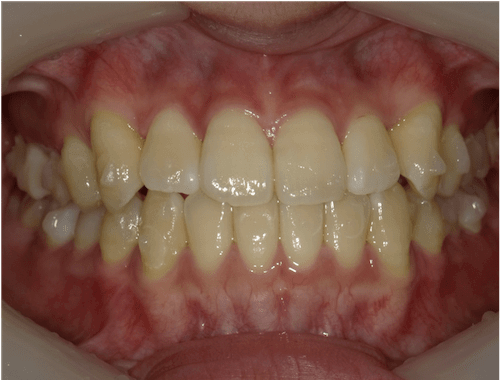

叢生(後戻り)

BEFORE

AFTER

担当医コメント

以前、一度矯正治療を受けたが後戻りにより歯並びに問題が出てきた。上下顎に叢生があり、上顎前歯が前突している。叢生量を鑑みてインビザラインでの治療が可能と判断した

治療の概要

年齢/性別

33歳 女性

主訴

前歯が出ているのが気になる。

一度矯正治療をしたがまた悪くなってしまったので綺麗に治したいでした。

リスク

歯肉退縮が起こる可能性がある。

費用

85万円

期間

10ヶ月

術前

術中

術後